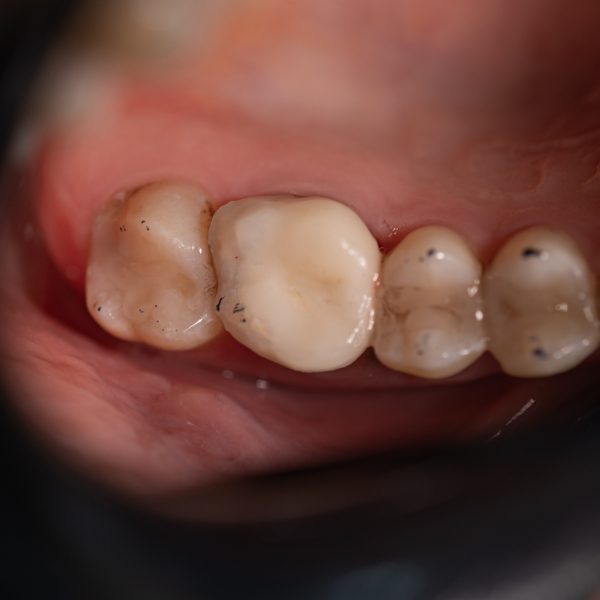

inlay&onlay glass ceramic (multi layer) cad

اینلی و آنلی یا اصطلاحا اینله و آنله نوعی درمان ترمیمی دندان هستند اینها نوعی روکش محسوب می شوند که در مواقع پوسیدگی و شکستگی دندان از آنن ها استفاده می شود. احتمالاً شنیده اید که روکش‌ها یا مواد پرکننده برای پر کردن حفره‌ها و پوسیدگی دندان قرار داده می‌شوند. با این حال، ممکن است در مورد برخی از جایگزین‌ها مانند اینله و انله دندان نشنیده باشید. فرق اینله و آنله در این است که برای پر کردن حفره های کوچک از اینلی و پر کردن حفره های بزرگ تر به طوری که لبه ی دندان را هم شامل شود از آنلی استفاده می شود. این قطعات با توجه به قلبی که از دندان گرفته شده، در لابراتوار ساخته و بر روی دندان نصب می شوند.

اینلی و آنلی شبیه به روکش های تمام سرامیک هستند اما تراش آنها بسیار کمتر از روکش بوده و در واقع روکش نصفه هستند. اینلی و اونلی برای درمان دندان هایی که نسج زیادی از دست داده اند و امکان ترمیم مناسب آنها به طور مستقیم با کامپوزیت نبوده و در عین حال نسج آنها آنقدر ضعیف نشده که نیازمند روکش باشند، استفاده می شود.